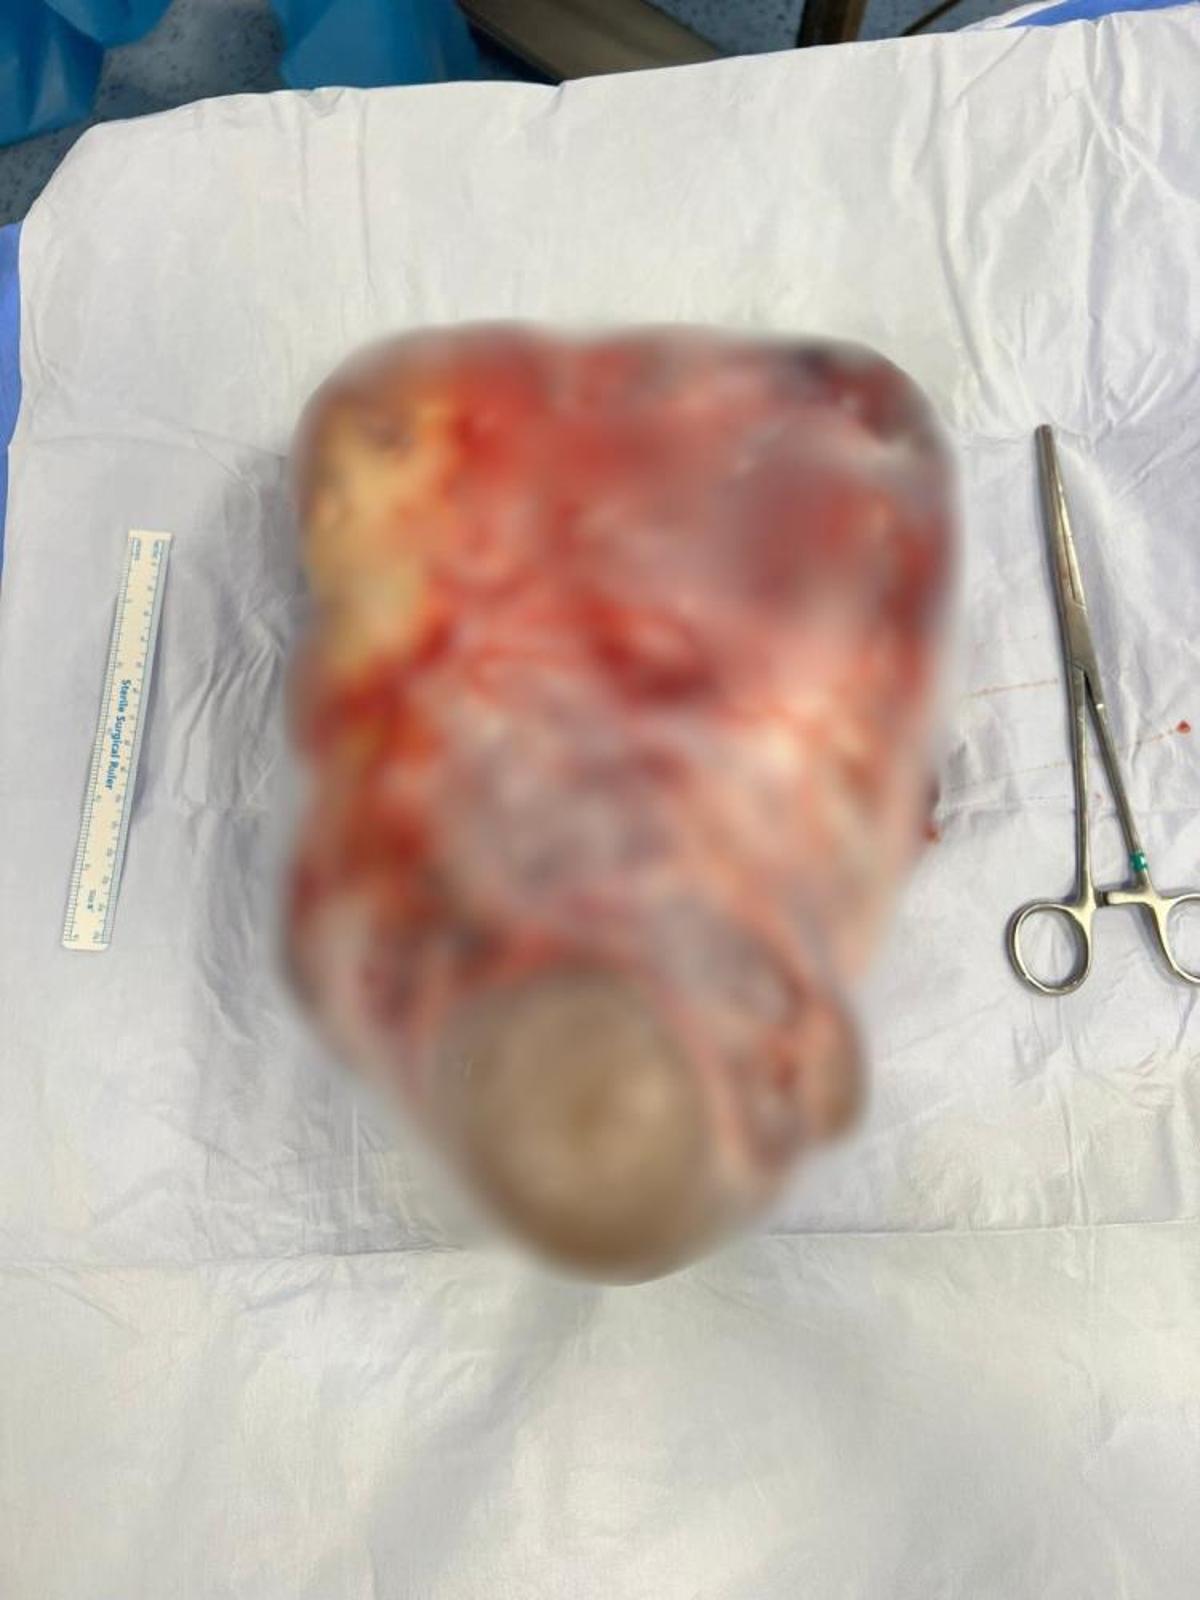

Biruni Üniversitesi Tıp Fakültesi Hastanesi Kadın Hastalıkları ve Doğum Uzmanı Dr. Öğr. Üyesi Serhat Şen, hastanın tanı sürecinin zorluklarına dikkat çekerek, "Hasta bize geldiğinde karnı oldukça şiş ve zayıflamıştı. Daha önce bağırsak problemi sanılarak diyet önerilmiş. Yumurtalıktan kaynaklanan kitleler genellikle sindirim sistemi rahatsızlıklarıyla karıştırılabiliyor. Bu nedenle hasta da bir süre özel beslenme programıyla durumu idare etmeye çalışmış. Meslek hayatımda gördüğüm en büyük kitleydi. Karın içinde geniş bir alan olduğu için fark edilmesi zor olabiliyor" dedi.

Hastanın ameliyat süreci hakkında bilgi veren Dr. Öğr. Üyesi Serhat Şen, "Kitle, bağırsakları sıkıştırdıkça kendine yer bulabiliyor. 40-45 santimetreye ulaşmasa da 10-15 santimetreye büyüdüğünde belirtiler ortaya çıkmaya başlıyor. Belirtilerin geç fark edilmesinin nedeni, hareketsiz yaşam tarzı ve düzenli kontrole gitmemesi. Çok hareketsiz kaldığımızda bedenimizdeki değişimleri anlamakta zorlanabiliyoruz. Yıllık kontroller, özellikle adetten sonra ultrasonla yapılmalı; bu çok önemli. Bu kadar geç fark edilmesi nadir bir durum ancak olabildiğini göstermesi açısından çarpıcı" dedi.

"AMELİYAT 20-25 DAKİKA SÜRDÜ"

"Ameliyatlarda ekip çalışması kritik önem taşıyor" diyen Dr. Öğr. Üyesi Serhat Şen, "Üniversite hastanesi olmamız nedeniyle elimiz güçlü. Ameliyata, organ korumaya yönelik hazırlıklı giriyoruz. Karnı diklemesine kestiğimiz prosedür 20-25 dakika sürüyor ve kitle hızlıca çıkarılıyor. Hastanın yaşı genç, bu nedenle kanser beklemiyoruz. Ameliyat hem güzel hem de hızlı geçti. Hasta artık yürüyebiliyor ve normal sürecine döndü. Yarın evine gidecek, bir hafta sonra işine başlayacak. Korkulacak bir durum yok" şeklinde konuştu.

Dr. Öğr. Üyesi Serhat Şen, "Hastanın belirttiği dört ay kitleyi fark ettiği süreyi kapsıyor. Gerçek süreyi söylemek zor, en az bir yıl sürmüş olabilir. Kitle büyüdükçe çevresindeki kapsül inceliyor. Bir travma (örneğin yumruk ya da çarpma), kapsülün patlamasına ve içeriğin karın içine boşalmasına neden olabilir. 4-15 santimetre arasında kitle dönebilir ve çürüme başlayabilir. Ani ağrı veya kanama da görülebilir. Yumurtalığa yapılan her müdahale rezervden bir miktar eksiltir" dedi.

Bu vakada sağ yumurtayı tamamen çıkarmak zorunda kaldıklarını belirten Dr. Öğr. Üyesi Serhat Şen, "Çünkü sağlıklı doku kalmamıştı. Sol yumurtası ve tüpü sağlam; bu nedenle hastanın çocuk sahibi olmasında sorun yok. Yumurtalık cerrahisinde yüzde 100 rezerv koruması hedefleniyor ve bu çocuk sahibi olma ihtimalini engellemiyor. Müdahale ihtimali azaltsa da tamamen yok etmez. Korkuya gerek yok; müdahale gerekiyorsa yapılmalı" şeklinde konuştu.